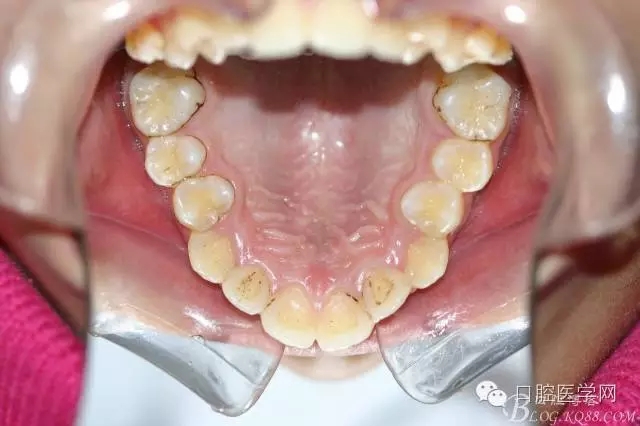

正畸查:替牙合。第一恒磨牙中性合。上牙弓尖圓型下牙弓方圓型。前牙覆合3度覆蓋7.5mm。下前牙咬到上舌側(cè)牙齦。上頜擁擠4.0mm,下頜擁擠

3.0mm。上頜稍前突下頜后縮,上下唇前突,上前牙覆蓋下唇,下唇外翻。面下三分之一過(guò)短,頦唇溝明顯,開(kāi)唇露齒,頦饜窩明顯。顳下頜關(guān)節(jié)開(kāi)閉口無(wú)彈響,無(wú)壓痛,開(kāi)口型開(kāi)口度正常。

正畸前照片: